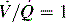

The ratio of lung volume to transpulmonary pressure is called compliance. Compliance of the lung (CL) is a measure of the distensibility of the lungs and is defined as the volume change (ΔV) produced by a transpulmonary pressure change (ΔP):

image

Compliance is high when the volume change produced by a given pressure change is large. Compliant lungs will inflate with very low pressure (i.e., the volume change produced by 1   cm H2O pressure is large).

If the volume change produced by a given pressure change is small, the lungs are stiff and less compliant. When lung compliance is low, the work of breathing is increased. Compliance is increased in diseases such as emphysema and asthma, and it is decreased by pulmonary edema, pneumothorax, atelectasis, and pulmonary fibrosis. Compliance is difficult to measure, but effective compliance or dynamic compliance of the lung and chest wall can be measured in the intubated child during mechanical ventilation (see sections, Optimal PEEP and Common Diagnostic Tests).